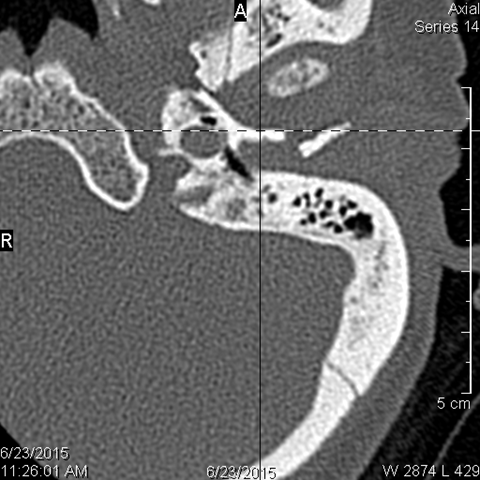

The ossicles, in particular the incus long process, the incudostapedial joint and stapes are fractured or dislocated. [Yes/No]

The facial canal including the labyrinthine, tympanic and descending portions and nerve are fractured. [Yes/No]